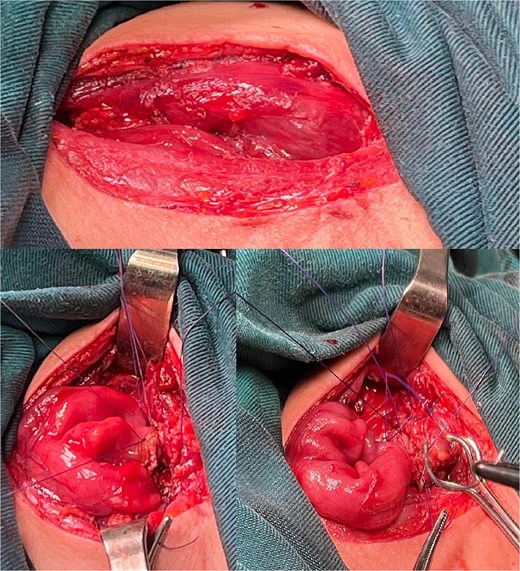

The right colon was mobilized using a standard Cattell–Braasch maneuver. Intraoperative assessment revealed the absence of the right colic artery; perfusion relied on the ileocolic artery and the right branch of the middle colic artery via a well-formed marginal artery of Drummond (Fig. 2). Temporary occlusion of the ileocolic vessels confirmed adequate collateral flow (Fig. 3). The terminal ileum was transected ~3 cm proximal to the ileocecal valve, and an incidental appendectomy was performed.

Confirmation of collateral vascular flow in the right colon (arrow shows ileocolic artery).

The prepared right colonic segment was transposed through the posterior mediastinum using the ‘shoe-shiner’ technique to avoid torsion and preserve orientation (Fig. 4). A hand-sewn, two-layer, isoperistaltic esophago-colonic anastomosis was performed in the cervical region using interrupted 4–0 polyglactin sutures for the mucosal layer and running seromuscular sutures for the outer layer (Fig. 5).

Alimentary tract continuity was re-established with a mechanical, side-to-side, isoperistaltic Roux-en-Y colojejunal anastomosis and a side-to-side ileotransverse anastomosis (Fig. 6). Two closed-suction drains were placed: one adjacent to the cervical anastomosis and another via the esophageal hiatus into the posterior mediastinum. Total operative time was 320 minutes, and estimated blood loss was 1000 ml.

Abdominal anastomoses. (A) Colo-jejunal anastomosis, (B) alimentary loop, (C) Roux-en-Y anastomosis, (D) ileo-transverse anastomosis.